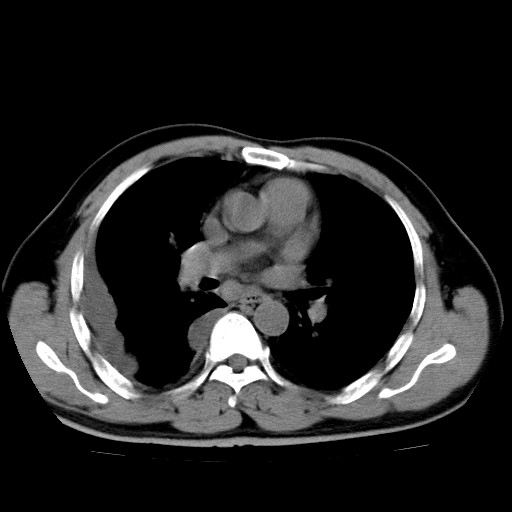

男,54岁,咳嗽,右侧胸痛10天。肺窗>150k,传不了

右肺中心型肺癌并右下肺不张,右侧胸膜纵隔转移。

右中央型肺癌并右肺下叶不张,纵隔内及右胸膜转移,右胸腔积液

考虑   右肺癌伴右下肺部分不张,阻塞性肺炎,纵隔淋巴结增大,右侧胸腔积液其他待排

考虑右肺下叶中央型肺癌并右肺下叶不张,纵隔淋巴结内及右胸膜转移。建议增强。

右下叶大片实变,肺门未见明显肿块影。有胸腔积液和纵隔内肿大淋巴结影。没有增强和肺窗,不好定。

考虑:1、右下叶周围型肺癌伴胸膜、纵隔淋巴转移?

右下叶大片性阻塞性肺炎,肺门未见明显肿块影,纵隔内可见肿大淋巴结影,右见右侧胸腔积液及右侧胸膜增厚。

考虑:右侧中心性肺癌?伴纵隔淋巴结转移。建议上传肺窗。